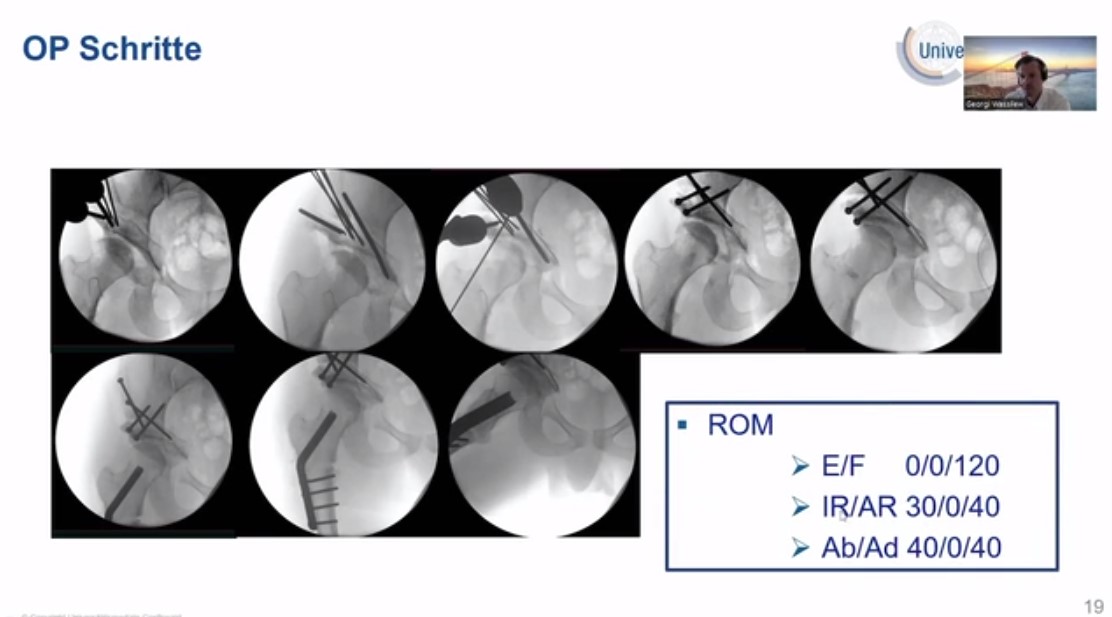

Complication Case: Modifizierte Dunn-OP bei einer Epiphyseolysis capitis femoris - Akut auf Chronisch S. Landgraeber